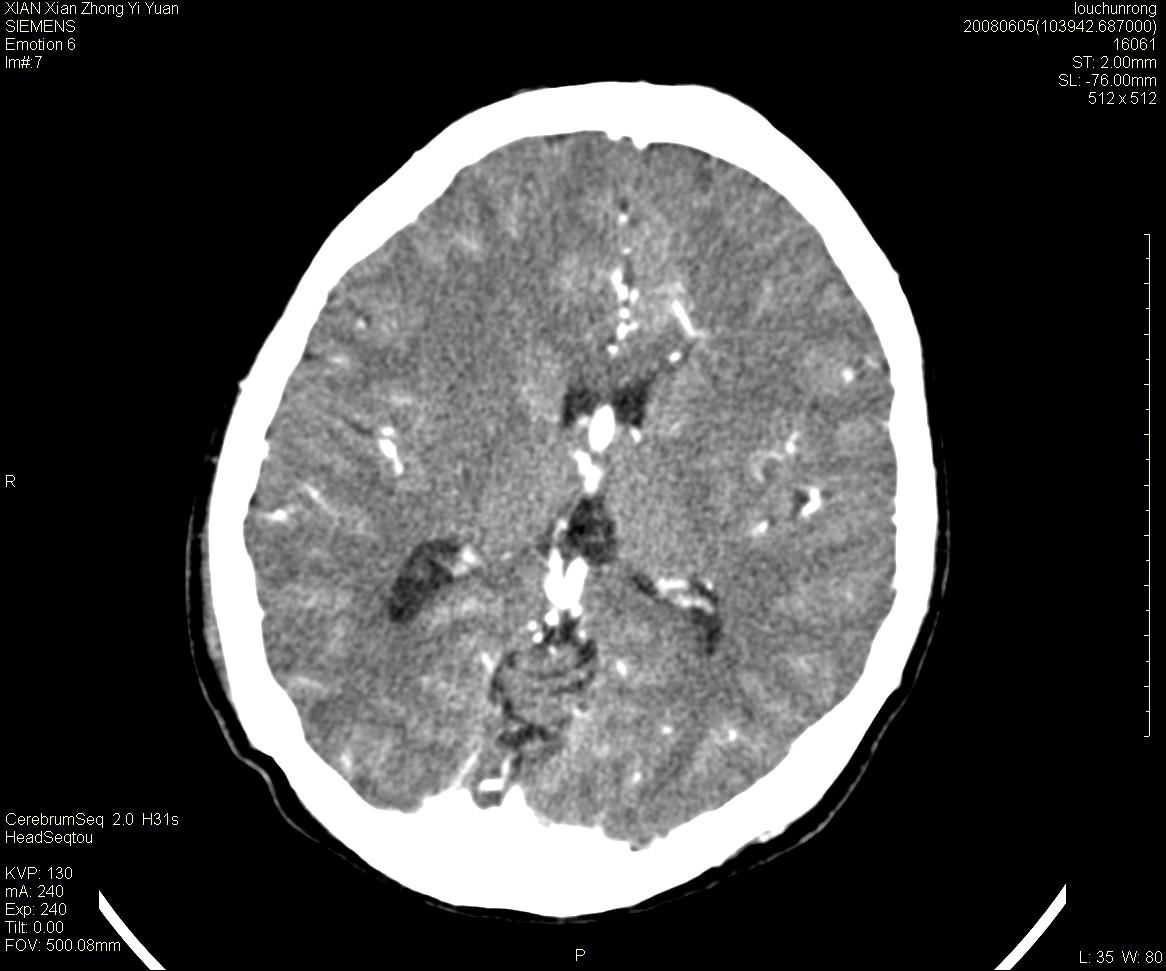

标题: CT13860:F52Y,,头外伤致头晕半天,以前无不适。 [打印本页]

标题: CT13860:F52Y,,头外伤致头晕半天,以前无不适。

层厚2mm。

左侧侧室内血管异常增粗,考虑血管变异或血管瘤可能,余未见异常

大家看左额叶大脑镰旁高密度影

中线附近、枕叶近枕骨处及脑内多发点条状强化影,考虑血管异常?

大脑大静脉池内的密度不均,双侧脑室增宽,我看右异常这块。战友们看看